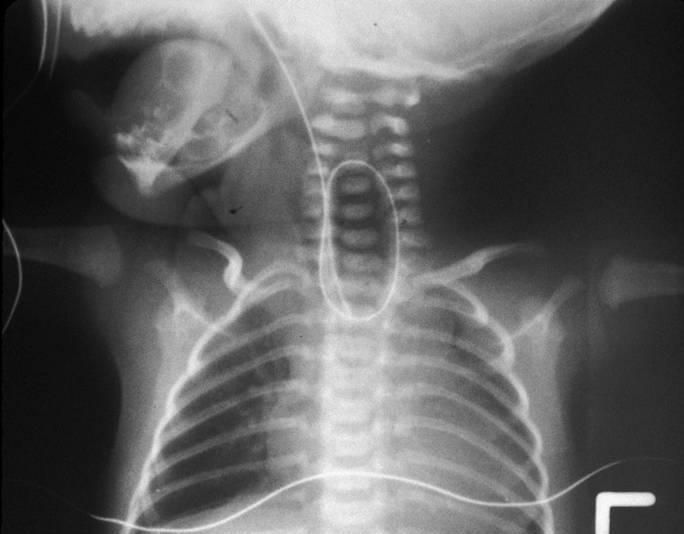

Tracheoesophageal fistula is a condition in which there is abnormal communication between the trachea and esophagus. It occurs because of a congenital defect in the separation of tracheal diverticulum and foregut during embryogenesis. In one of the commonly occurring variants, the distal esophagus communicates with the trachea while proximal esophagus ends in a blind pouch. In this case, an attempt to pass a nasogastric tube is unsuccessful. Due to an absence of a distal passageway, it ends up coiling in the proximal esophagus. Surgical correction is required. Image via: https://step2.medbullets.com/pediatrics/120608/transesophageal-fistula